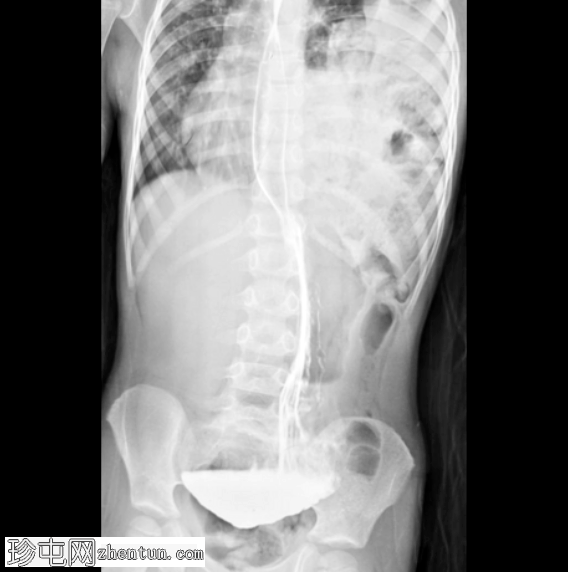

CT

冠状面

非造影

左侧膈疝通过位于左膈中部的一个缺损形成,伴有纵隔向右侧移位,下方左塌陷。

脾脏、大肠和小肠均有疝气,同时伴有肠系膜上血管疝气。

胃位于下部,靠近主动脉分叉处。

在降结肠和直肠中可见先前荧光透视检查的残留造影剂。